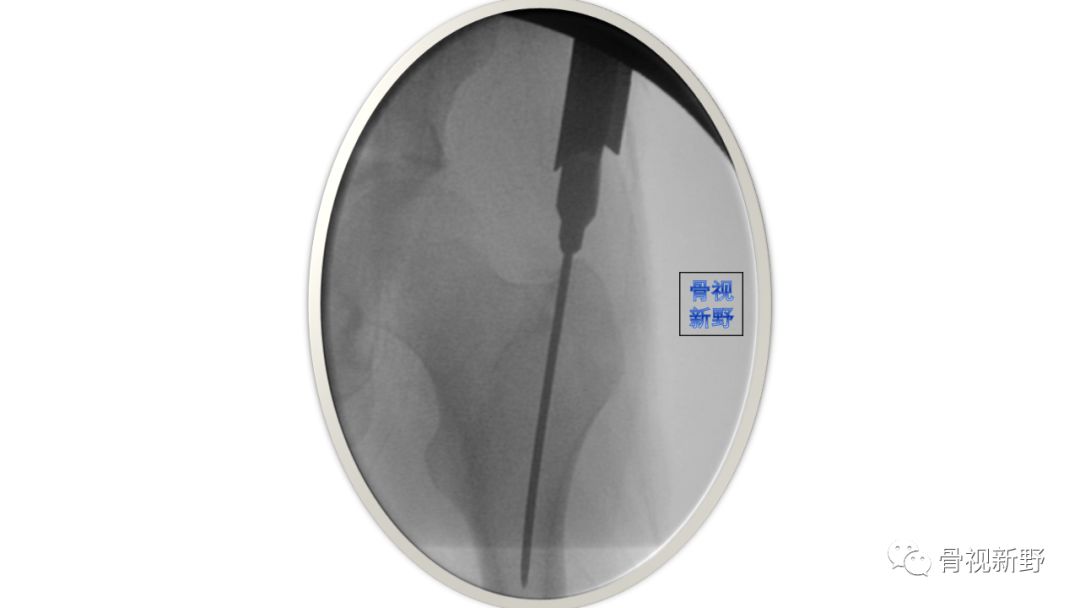

不要对未复位的骨折进行扩髓

由于股骨近端髓腔较宽、骨质较疏松,粗隆间骨折不像长骨干骨折,复位不良是不会通过扩髓或插钉而改善,因此不要对复位不良的粗隆间骨折进行扩髓和插钉。扩髓、插钉前骨折复位啥样、之后还是啥样。

如果骨折不能闭合复位,建议经皮或辅助小切口,通过骨钩、顶棒、复位钳进行复位,然后再进行扩髓。